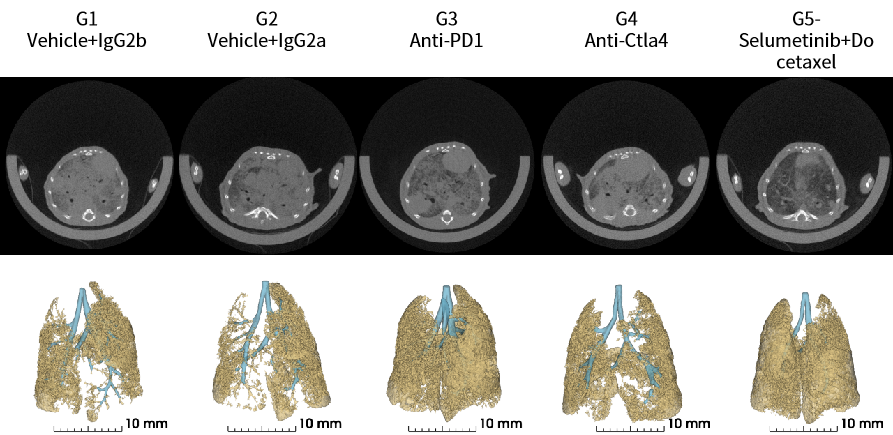

Trp53-Flox/Kras-LSL-G12D小鼠是一种原发肺癌小鼠模型,包含了KRAS基因突变与Trp53蛋白缺失。编码肿瘤抑制因子Trp53在绝大多数小细胞肺癌 (SCLC) 肿瘤中失活。野生型Kras激活/失活效应是受控的,而突变型Kras蛋白功能异常,持续处于激活状态,导致肿瘤细胞的持续增殖。Kras 突变在肺癌(NSCLC)占34%,以非小细胞肺癌占比较多,肺鳞癌中占比较少。KRAS突变基因与EGFP过表达基因的上游含有lox-stop-lox终止序列,其在没有cre重组酶的条件下是不表达的。通过使用AAV-CRE对小鼠进行诱导,即可使小鼠产生肿瘤。

验证数据:

图3 Trp53-Flox/Kras-LSL-G12D原发肺癌小鼠模型可通过AAV-CRE诱导引发肺癌。